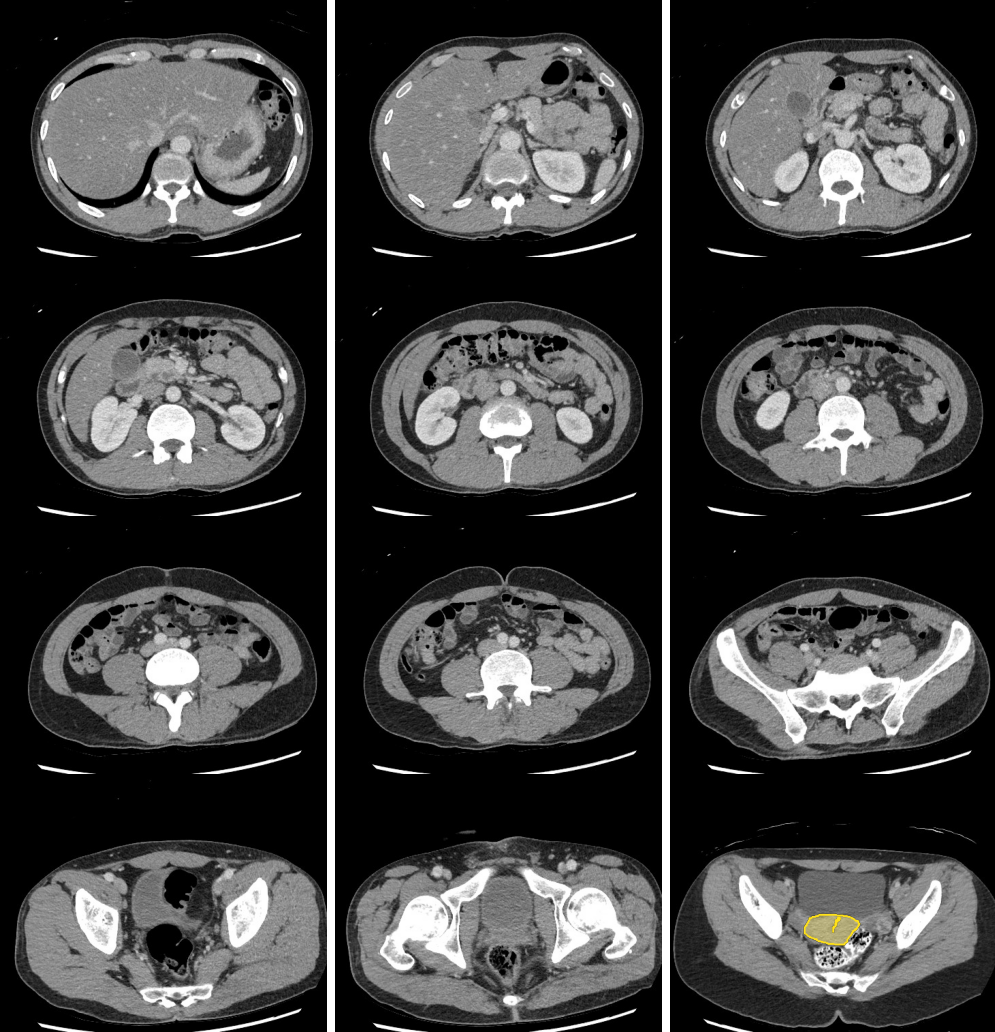

Slice 1

Slice 2

Slice 3

Slice 4

Slice 5

Slice 6

Slice 7

Slice 8

Slice 9

Slice 10

Slice 11

Slice 12